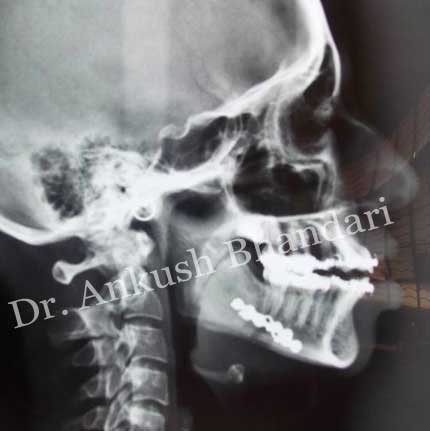

- The details of the surgery performed will depend on what you are having done and will be explained to you by your oral and maxillofacial surgeon.Surgery might aim to reposition part or all of the top and/or lower jaw.The surgeon gains access to the bones inside the mouth via the gums. Once the areas of bone have been revealed and loosened they are moved into a new position and fixed in position with small metal plates and screws, which usually remain in the bone. Sometimes these plates will be removed later, which will mean another operation. The jaw position is also maintained using a thin, clear plastic splint (or wafer), which sometimes remains secured to the lower teeth for some weeks. We use dissolving stitches to neatly close up the gums.